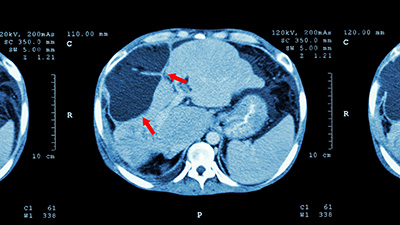

tomografia figado bxA isquemia hepática remanescente é preditiva de menor sobrevida livre de recorrência e menor sobrevida câncer específica em pacientes submetidos à ressecção cirúrgica para metástases hepáticas de tumores colorretais. É o que mostram dados recentes de Yamashita e colegas1 do MD Anderson, em trabalho comentado por Elizabeth Bourd no Lancet Oncology2.

Yamashita e colegas utilizaram retrospectivamente dados de 629 pacientes submetidos à ressecção hepática para metástases do câncer colorretal, operados no MD Anderson entre 1º de janeiro de 2008 e 31 de dezembro de 2014. Dessa população, 202 tinham tomografia obtida dentro de 30 dias após a cirurgia. As imagens foram avaliadas de forma retrospectiva por radiologistas, que classificaram a isquemia no fígado no pós-operatório, considerando diferentes escores: isquemia inexistente (grau 0; n = 105), marginal (grau 1; n = 47), parcial (grau 2; n = 45), segmentar (grau 3; n = 5), e necrótica (grau 4; n = 0).